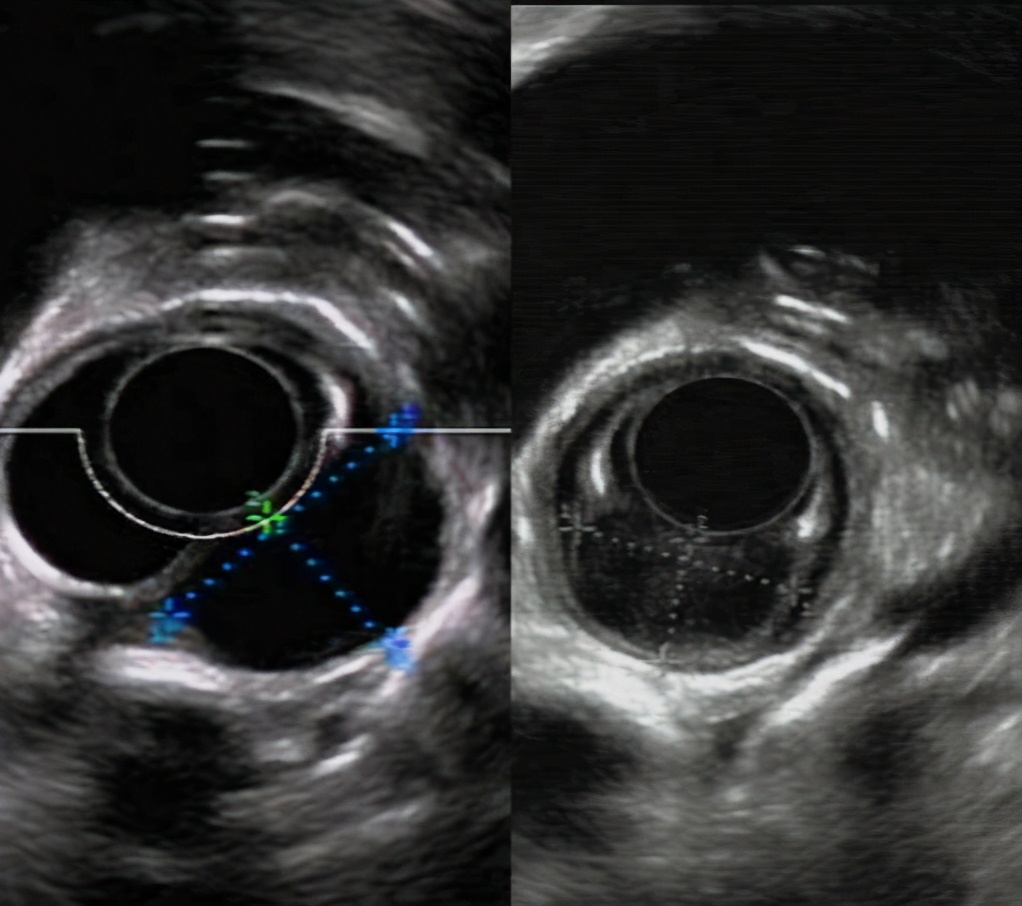

在朋友的推荐下,杨先生来到哈医大一院,经过腔镜肿瘤外科李军教授,消化内科徐洪雨教授及胸外科姜久仰教授等多学科专家会诊。徐洪雨教授通过超声内镜检查,提出"可以尝试通过内镜黏膜下隧道技术切除肿瘤,而且可以通过一条隧道切除两个肿物"的手术方案。

内镜下经隧道肿物切除术(STER)创造性地巧妙利用消化道黏膜和固有肌层之间的空间建立"隧道"进行操作,创伤小,术后无体表疤痕,既能充分体现"微创治疗"的优越性,更因术后患者恢复快,住院时间短,治疗费用低,可以大大减轻患者的家庭负担和医保资源。同时,徐洪雨教授分析患者食管肿物位于食管中上段固有肌层,直径为2.5cm,突向纵膈生长,比邻气管及胸主动脉,术中出现气胸、纵膈气肿、气腹、出血的风险较大,更存在切除第一个肿物后出现气胸而无法切除第二个肿物的后续风险。